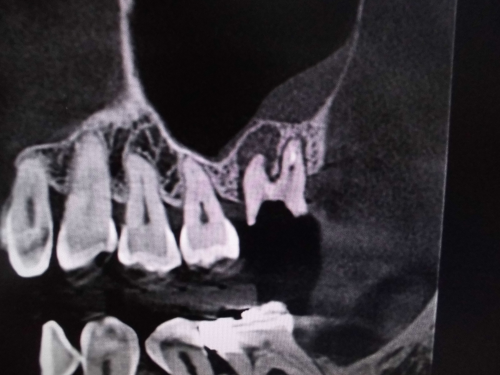

左上奥歯が割れています。一般的なレントゲンではわかりません。

CTでは破折線がはっきり見えます。患者様も納得しやすいです。